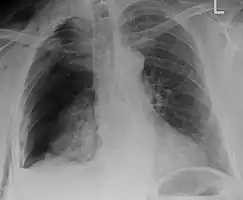

Right sided pneumothorax and rib fractures